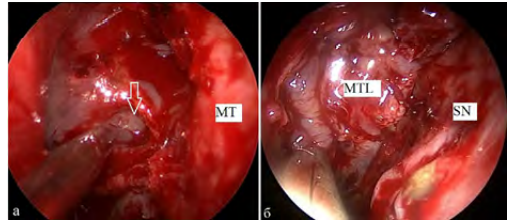

Рис. 1. Фото операционной раны: осмотр полости носа через эндоскоп справа (0 °): а) дефект основания черепа в области крыши решетчатого лабиринта справа (указан стрелкой); б) широкая фасция бедра (FL) расположена в области дефекта крыши решетчатого лабиринта справа. SN — перегородка носа, MT — средняя носовая раковина

Рис. 2. Фото операционной раны: осмотр полости носа через эндоскоп слева (0 °): а) дефект основания черепа в области ситовидной пластинки слева (указан стрелкой); б) назосептальный лоскут (NL), расположенный в области ситовидной пластинки после удаление менингоэнцефалоцеле слева. SN — перегородка носа, MT — средняя носовая раковина

2. Ротированная средняя носовая раковина (n = 4) — проводили частичное рассечение хрящевого основания средней носовой раковины и перемещение ее в область дефекта. Кровоснабжение лоскута сохранялось за счет передней решетчатой артерии. Метод применялся при дефектах в области крыши решетчатого лабиринта, ситовидной пластинки (рис. 3).

Рис. 3. Фото операционной раны: осмотр полости носа через эндоскоп справа (0 °): а) дефект основания черепа в области крыши решетчатого лабиринта после удаления менингоэнцефалоцеле справа (указан стрелкой); б) ротированная средняя носовая раковина (MTL), расположенная в области дефекта. SN — носовая перегородка, MT — средняя носовая раковина